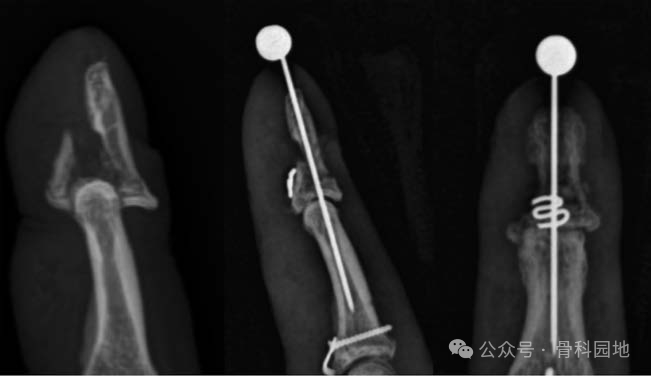

在C臂引导下骨折复位,通过调整背侧或掌侧骨块的位置进行骨折复位,并使用巾钳或类似器械临时固定。一旦复位达到满意,一枚克氏针在C臂引导下纵行固定远端指间关节。

在掌侧远端指间关节褶皱处做“Z”字形切口。 圆形针从背侧插入掌侧(如图)

在C臂引导下,通过牵拉缝线使背侧骨块充分复位。一旦观察到满意复位效果,将缝线紧密结扎于掌侧屈肌腱附着点。